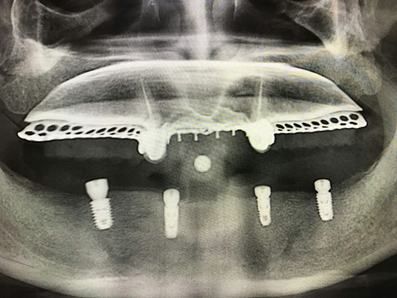

毛國(guó)斌種植病例——群討論分享